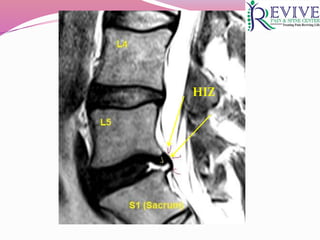

PATHOPHYSIOLOGY

 Normal disc : innervation & vascularity is limited to the

outer 1/3rd of the AF

 Injury  annular tears  vascularised granulation

tissue that extend from the NP to AF (HIZ on MRI)

 Granulation tissue : ↑ pro inflammatory molecules

(substance P)  maintain hyperalgesia  chronic pain

 Presence of HIZ in posterior annulus on T2

Imaging - DDD

HIZ